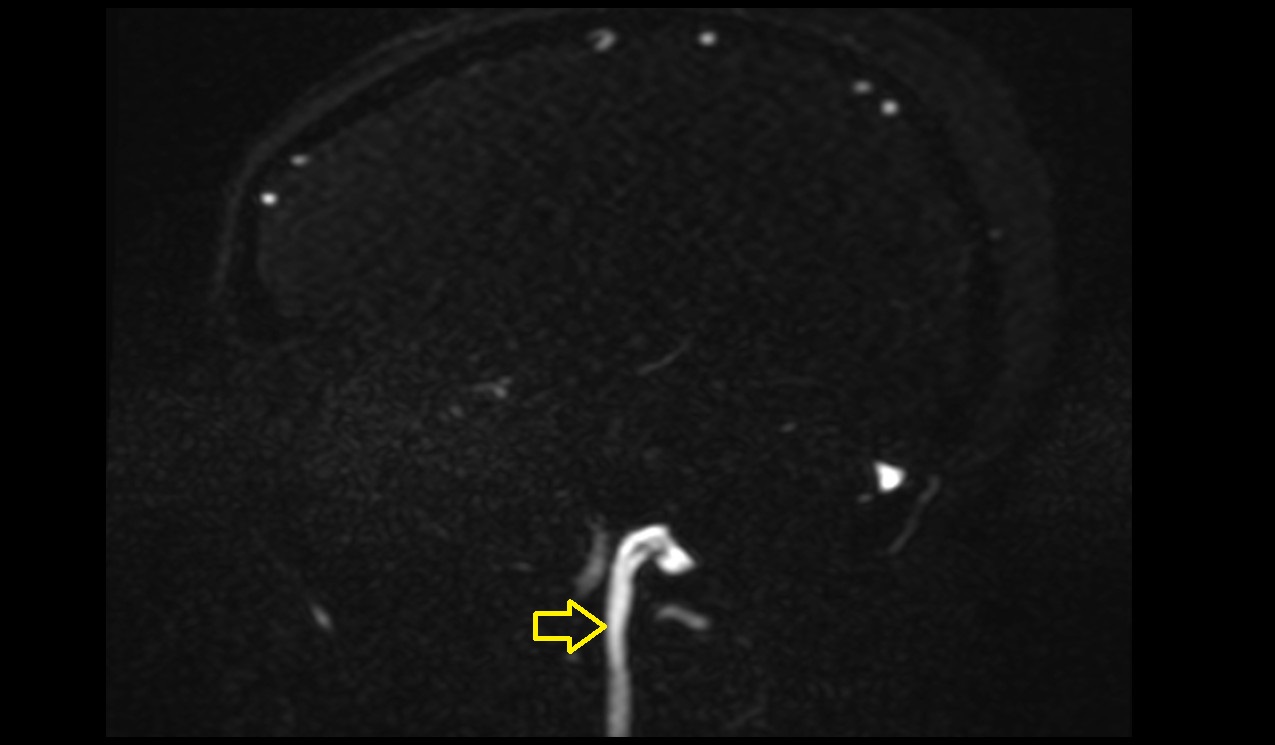

- Right vertebral artery

- Left vertebral artery

- Right vertebral artery (cervical part)

- Right vertebral artery (atlantic part)

- Right Vertebral Artery (Intracranial Part)

- Left Vertebral Artery (Intracranial Part)

- Left vertebral artery (atlantic part)

- Left vertebral artery (cervical part)